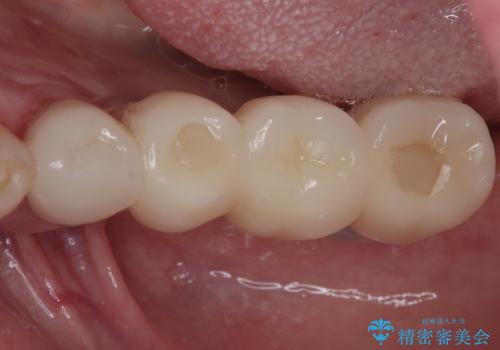

欠損の多い奥歯 インプラントによる補綴治療

右下の銀歯も気になるとのことで、インプラント治療と並行してオールセラミックによるブリッジ補綴治療も行うこととしました。

地元に戻られる前に無事に治療を終えることができました。

今後は東京出張のタイミングでメインテナンスに通院していただきながら、インプラントの状態をチェックしていくことになります。